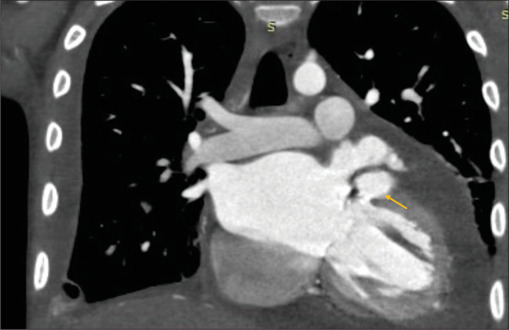

一名13岁女孩在因骨髓炎住院治疗后发生先天性二尖瓣感染性心内膜炎(IE)。临床过程中并发心肌内脓肿和严重的二尖瓣反流。嗜麦芽窄养单胞菌血培养呈阳性,这是一种罕见的IE病因,已知对用于治疗IE的一线药物具有耐药性,并有引起心肌脓肿的倾向。因此,对嗜麦芽葡萄球菌引起的心内膜炎的认识提高是有必要的。

A 13-year-old girl developed infective endocarditis (IE) on the native mitral valve after hospitalization for osteomyelitis. The clinical course was complicated by intramyocardial abscess and severe mitral regurgitation. Blood cultures were positive for Stenotrophomonas maltophilia, a rare cause of IE, which is known to be resistant to the first-line agents used for the treatment of IE, and has a propensity to cause a myocardial abscess. Hence, an increased awareness regarding endocarditis due to S. maltophilia is warranted.